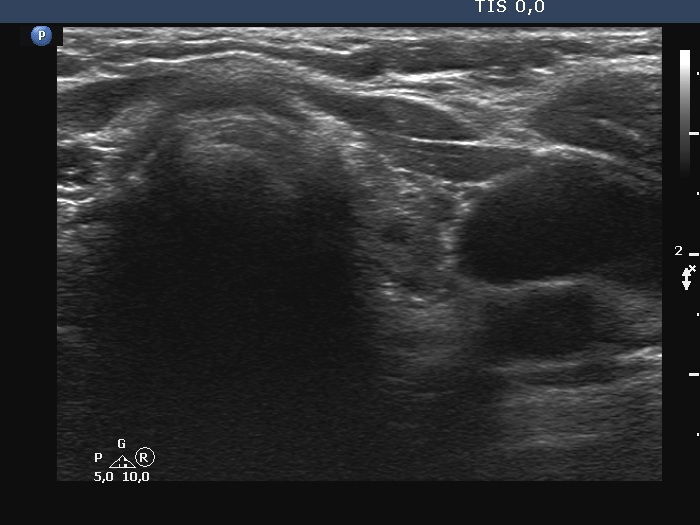

Ultrasonography. The right lobe was substantially enlarged and hypoechoic. It had macrocalcifications. The issue was whether the lobe was composed of a large nodule or only diffuse enlargement was present. The left lobe was much smaller. This lobe was also hypoechoic but to a lesser extent as was the right lobe. The vascularity was increased in the right while decreased in the left lobe.

The issue was whether the lobe was composed of a large nodule or only diffuse enlargement was present. On some still images, it seemed evident that there was a nodule. But we should never forget, that the reality is much more represented by videos. When we stop the continuous scan significantly affects what we see in a still image, which can therefore very easily be misleading. In the video, I highlighted those features on which we could decide considering only the ultrasound presentation that this very likely a nodule.